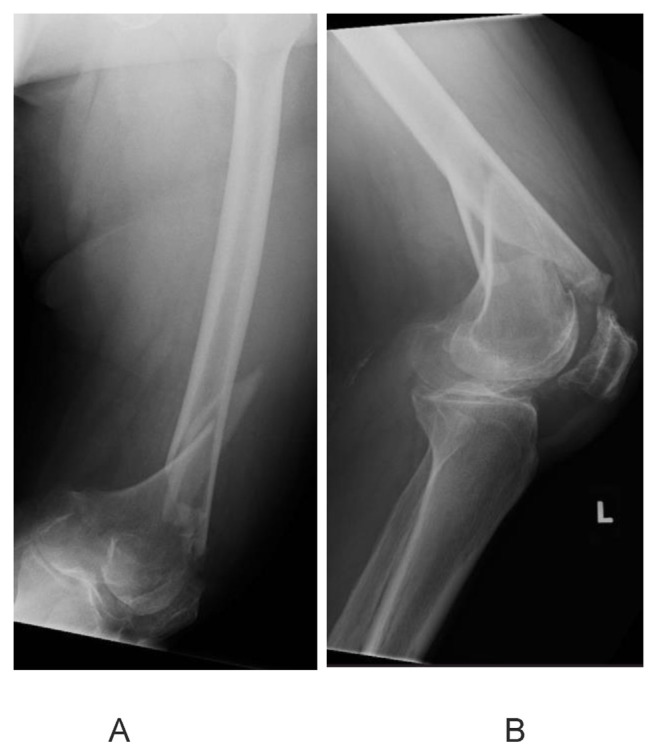

Introduction: Distal femur fractures result in high morbidity and mortality - comparable to that of hip fractures. The commonly used surgical fixation techniques today, locked plating and intramedullary nailing, have shown high postoperative complication rates. Thus, many surgeons temporarily keep patients non-weight bearing in the early postoperative stage. Increased time to ambulation after surgery is known to increase systemic complications in patients. We aim to investigate if an augmented fixation technique involving the use of a fibular strut allograft with dual locking plates helps to allow early mobilization postoperatively without adverse outcomes.

Methods: Five geriatric patients (four female, one male) with distal femur fractures (native or periprosthetic) were treated in our institution with the aforementioned technique, and were allowed early postoperative weight-bearing. These patients were followed up for postoperative outcomes. The primary outcomes studied were non union, implant failure and wound complications. Secondary outcomes studied include time to union, and Sander's functional score.

Results: There were no cases of non-union, implant failure or wound related infection. All patients achieved radiological union (mean = 12.6 weeks). Using Sander's functional scoring, two patients achieved excellent, two achieved good and one had fair outcomes. All patients were followed up for at least 6 months after operation.

Conclusion: Our method of augmented fixation with fibular strut allografts potentially allows for early weight bearing without adverse outcomes. Further studies with larger sample sizes are required to validate our findings.